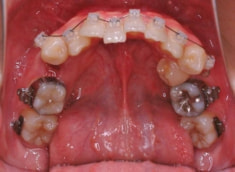

治療開始時

上下顎とも前突しており、叢生もあります。分析値からも抜歯対象症例です。

特に小臼歯部に叢生があり、8番(親知らず)も埋伏しています。8番と7番の接触部分に吸収が若干あるような所見が認められます。